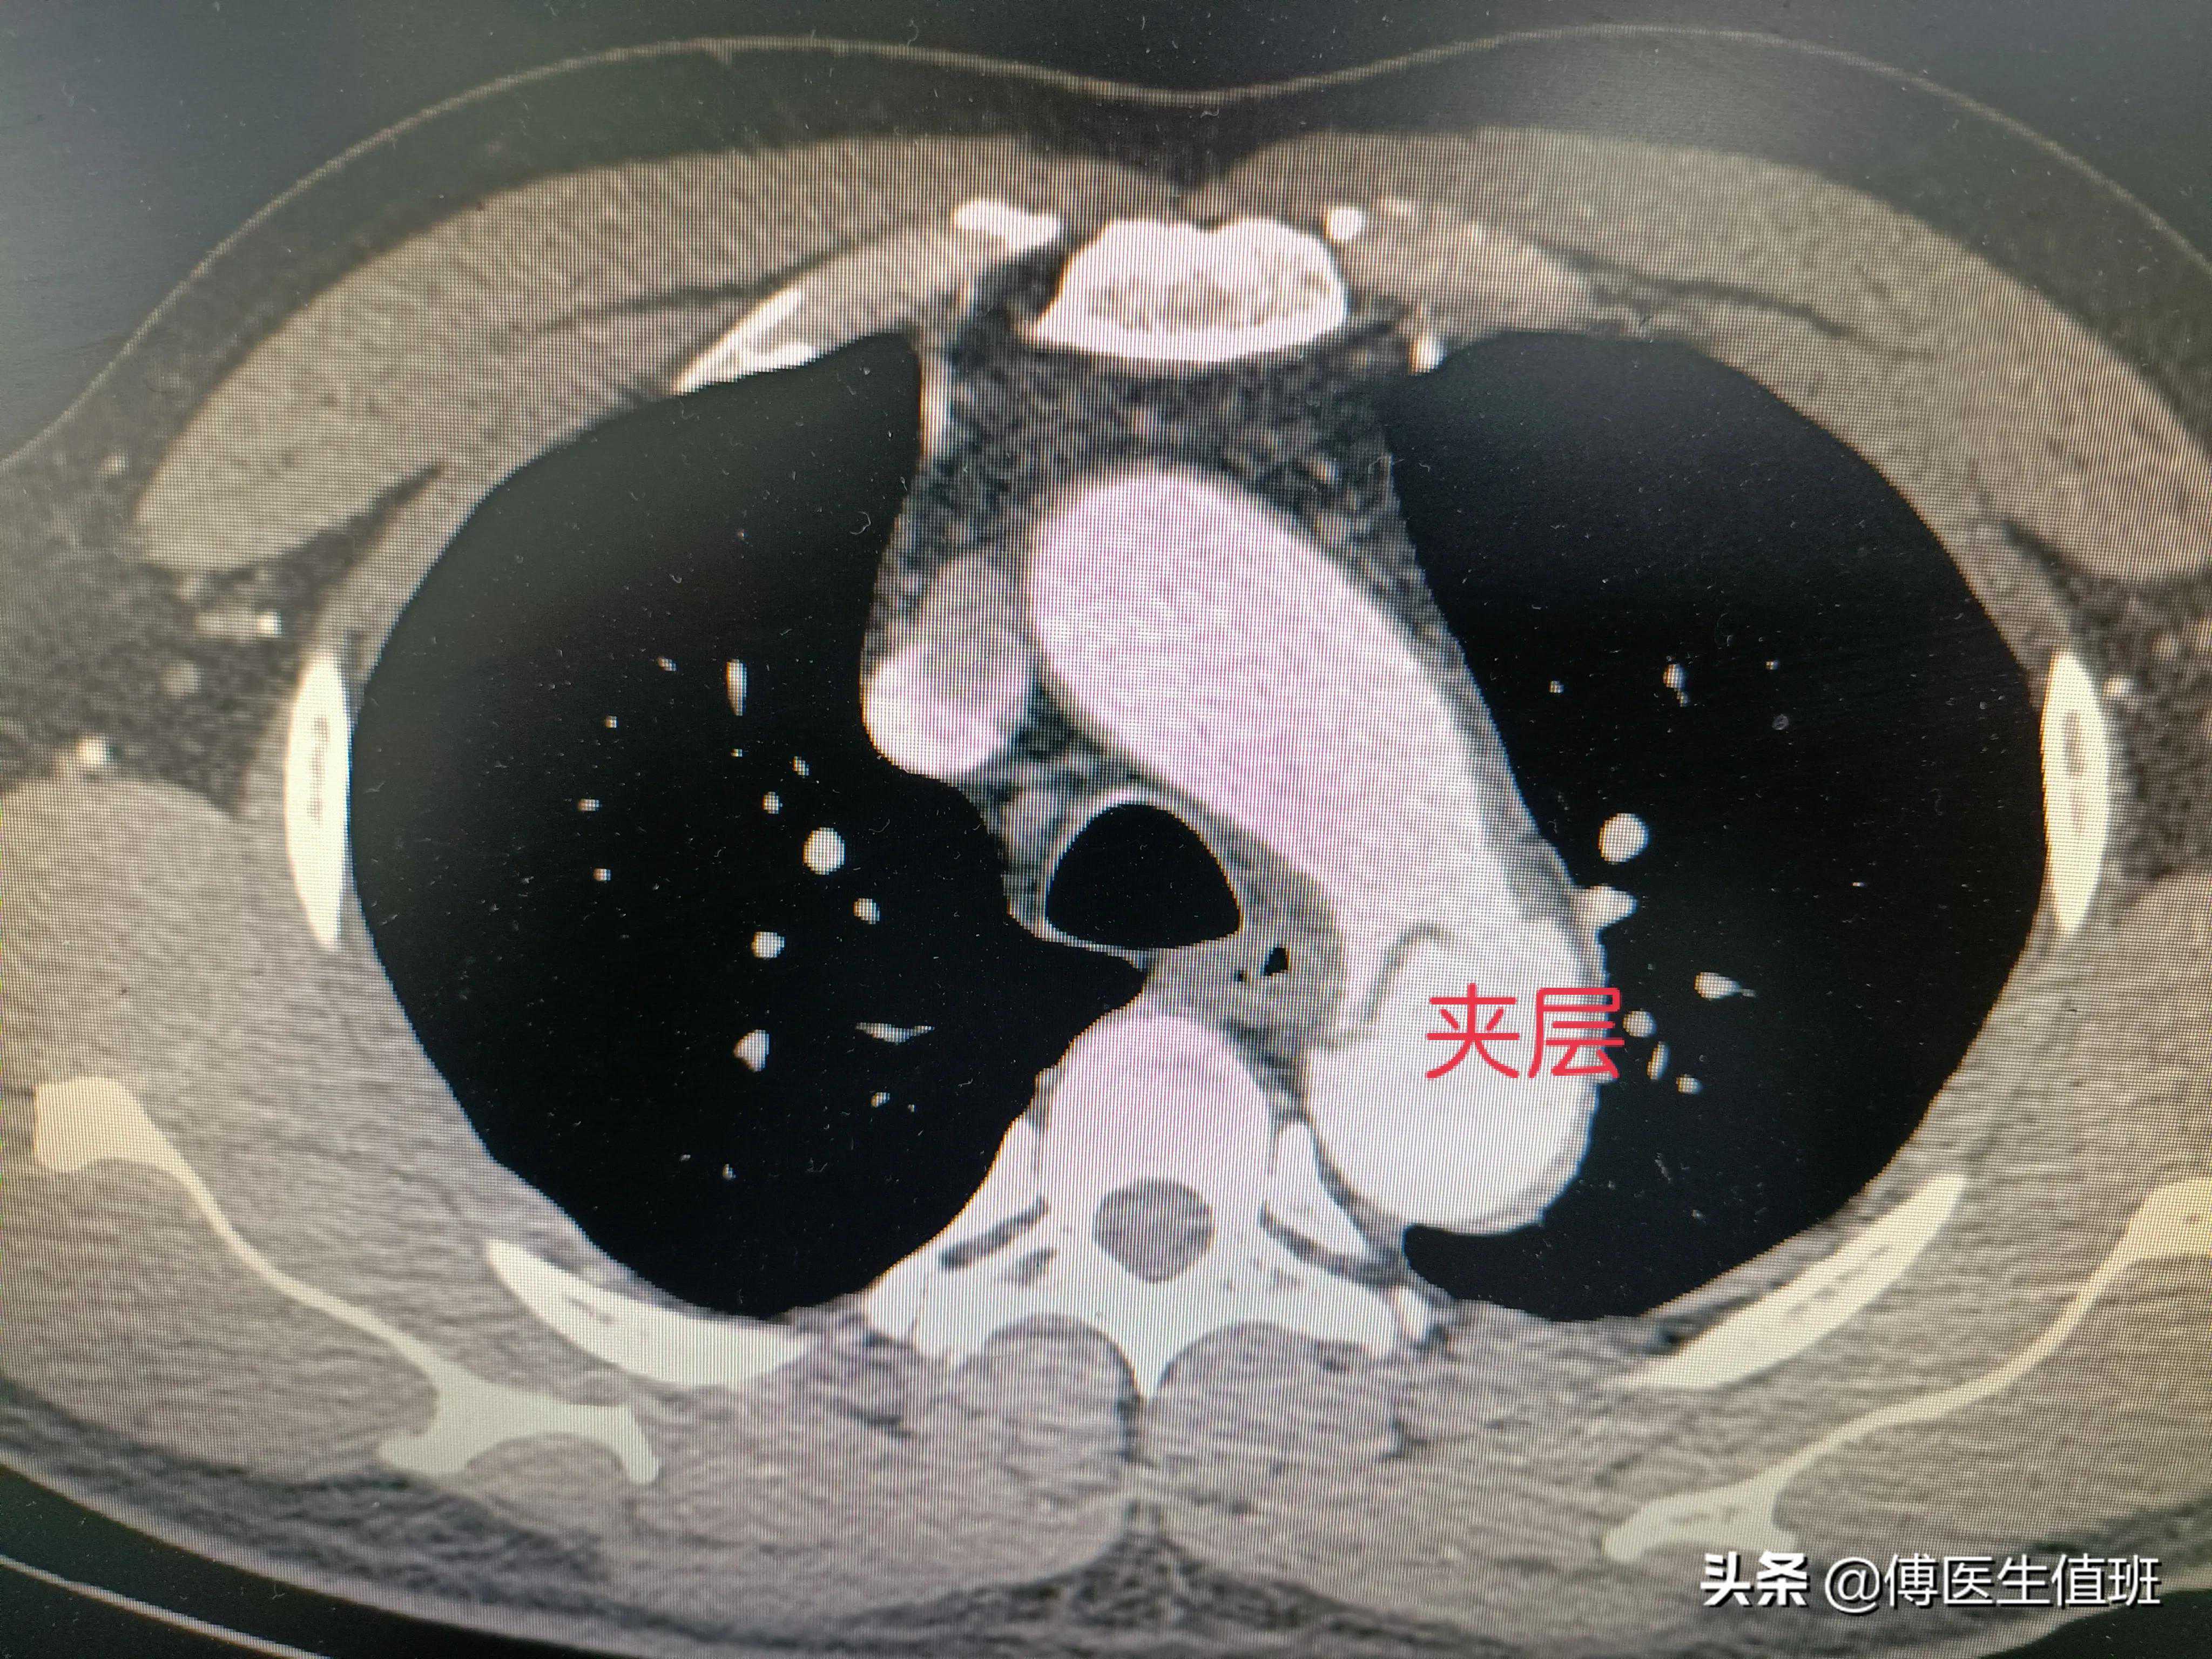

夹层?

主动脉明显增粗,应该是夹层,你看这里,主动脉壁两个层面,没错,是主动脉夹层。

属于哪个类型的主动脉夹层?

CT平扫判断困难,需要做增强扫描。CT室医师说。

主动脉走形迂曲、部分增宽,原发破口位于左锁骨下动脉远端,将主动脉分为两个腔,夹层累计大部分胸降主动脉和腹主动脉,右侧肾动脉起自于假腔,左侧肾动脉由真腔供血,肠系膜上动脉由真腔供血,腹腔干由真假腔供血。范围太广了,一直到腹主动脉全部撕裂。CT室医师说,属于IIIb型。